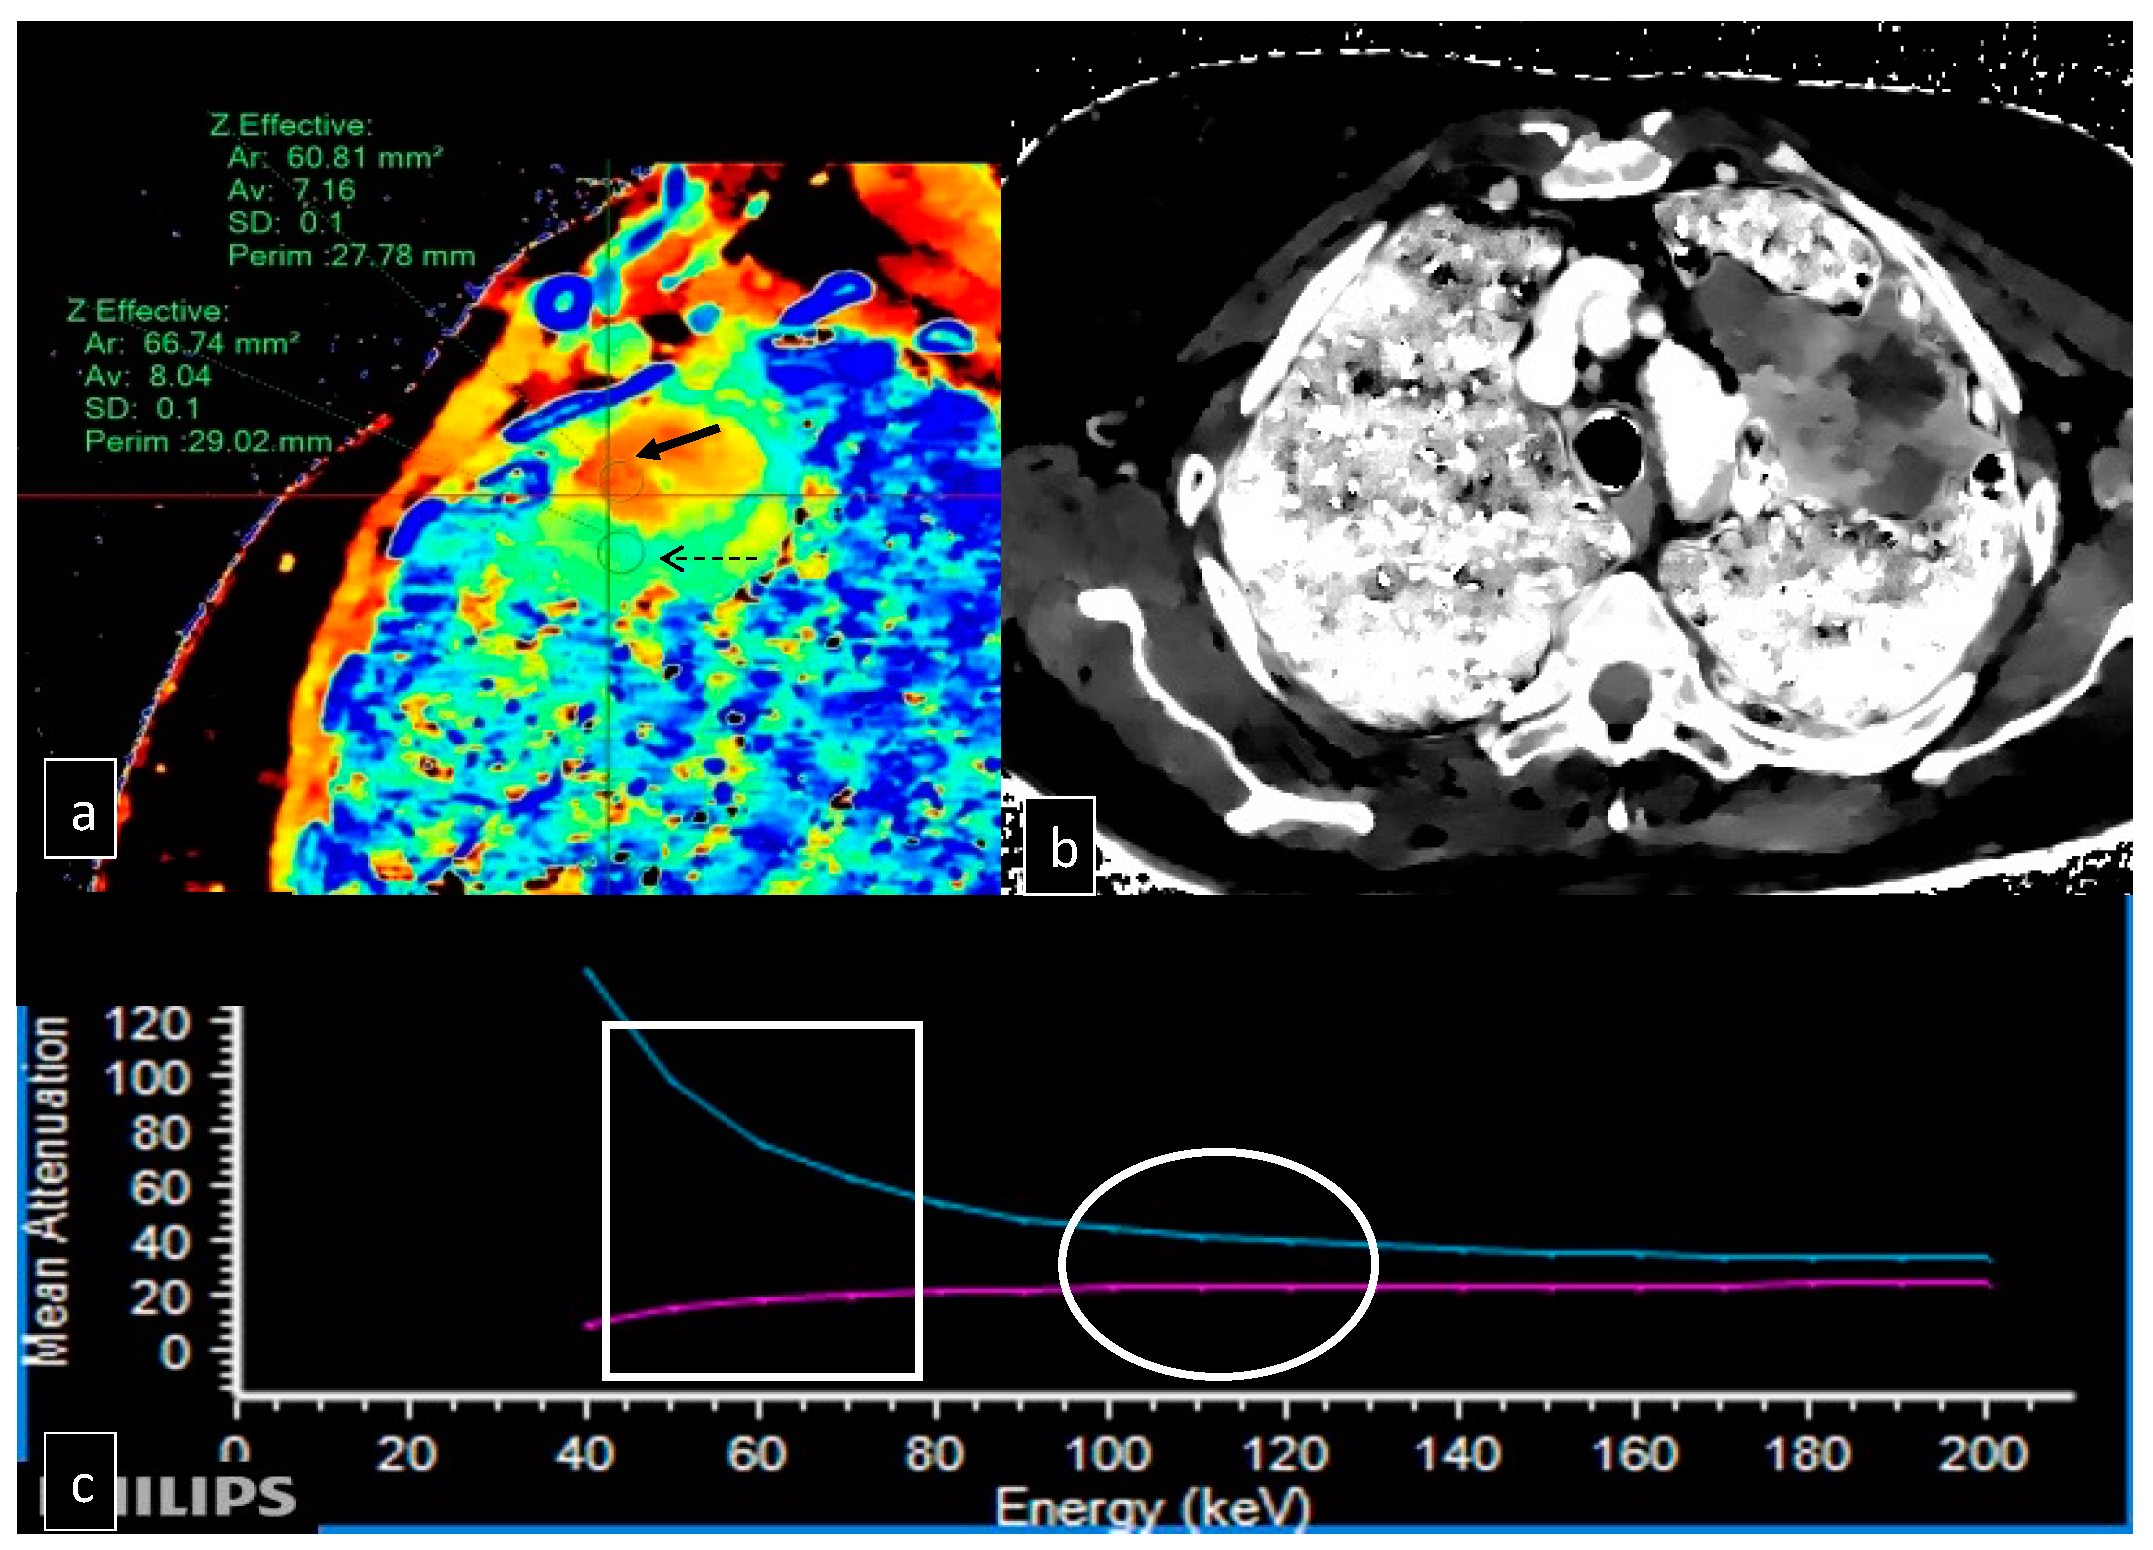

3. Results

- Curti, M.; Fontana, F.; Piacentino, F.; Ossola, C.; Coppola, A.; Carcano, G.; Venturini, M. Dual-layer spectral CT fusion imaging for lung biopsies: More accurate targets, diagnostic samplings, and biomarker information? Eur. Radiol. Exp. 2022, 6, 34. [Google Scholar] [CrossRef] [PubMed]